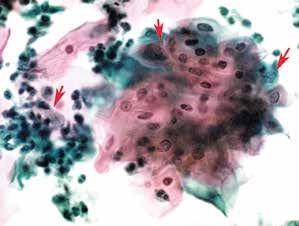

图4-10 低度鳞状上皮内病变(LSIL)(高倍、液基、巴氏染色)

细胞成片,大小形态不规则,胞核异型性明显。右上两个箭头为受累的鳞状上皮细胞,左箭头为反应性子宫颈管腺细胞。